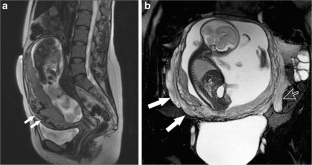

Fig. 1

Fig. 2

Fig. 3

Fig. 4

Fig. 5

Fig. 6

Fig. 7

Fig. 8

Fig. 9

Fig. 10